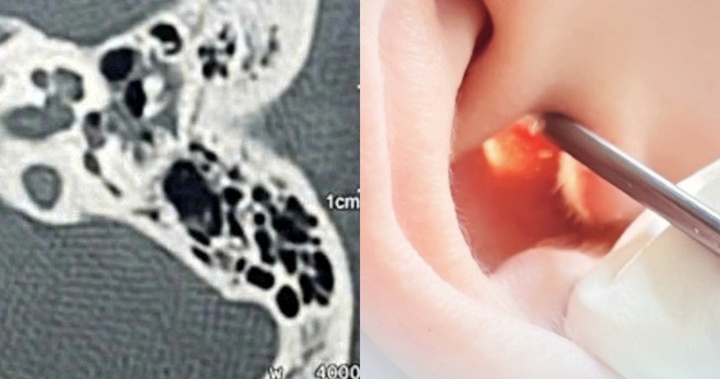

Một phụ nữ 44 tuổi đã phải nhập viện vì bị thương ở tai trái. Tai nạn xảy ra khi một đứa trẻ vô tình va vào tai người phụ nữ lúc cô ấy đang ngoáy tai.